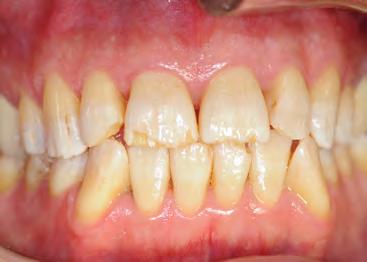

Two authors had access to the data and all information was de-identified. Study personnel made no contact with patients at any time throughout the study, and no PHI was recorded. Re corded data included diagnosis (clinical and/or pathologic), basic demographics (age, gender), and current prescription medica tions. For cases that were not biopsy-proven, the standard clinic protocol is that the clinical presentation must exhibit the charac teristic white Wickham striae for a patient to be given the clinical diagnosis of OLL or OLP (Figure 1). Any clinical diagnosis of OLL or OLP was rendered by one of four oral medicine experts in the Oral Medicine Clinic, and biopsy was performed in cases with any doubt.

Figure 1. Example of characteristic Wickham striae and reticular pattern on buccal mucosa used to clinically diagnose OLL and OLP cases. Erythematous areas also seen. Figure 2. Frequency and percent of study patients using specific medications with color-coded drug classes.